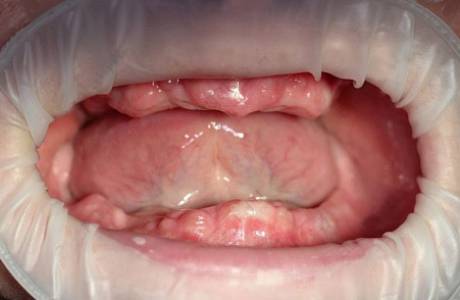

До лечения

Пациентка обратилась к врачу с полным отсутствием зубов.

После лечения

Были изготовлены и зафиксированы металлокерамические зубные мостовидные протезы на обе челюсти на имплантах. Пациентка очень довольна и красиво улыбается.